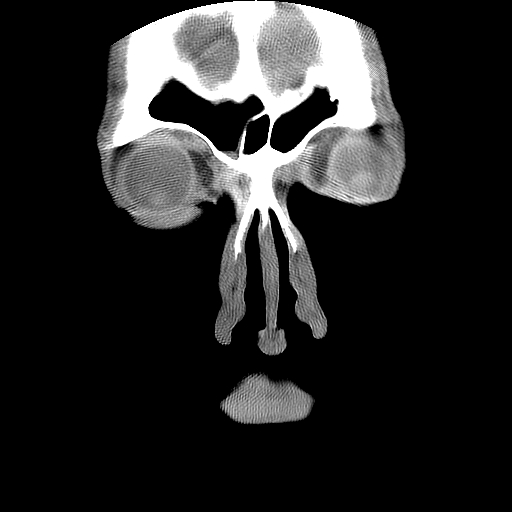

男,38岁,鼻塞、头痛2个月,要求鼻窦ct检查。

右侧上颌窦、蝶窦、筛窦、额窦及左侧上颌窦慢性炎症。

右侧鼻中隔左偏,右侧上颌窦、筛窦、额窦慢性炎性病变。右侧上颌窦开口粘膜增厚。

1)副鼻窦炎。2)右侧中鼻道及总鼻道粘膜息肉样变。3)双侧中下鼻甲肥大。4)鼻中隔轻度左突偏曲。